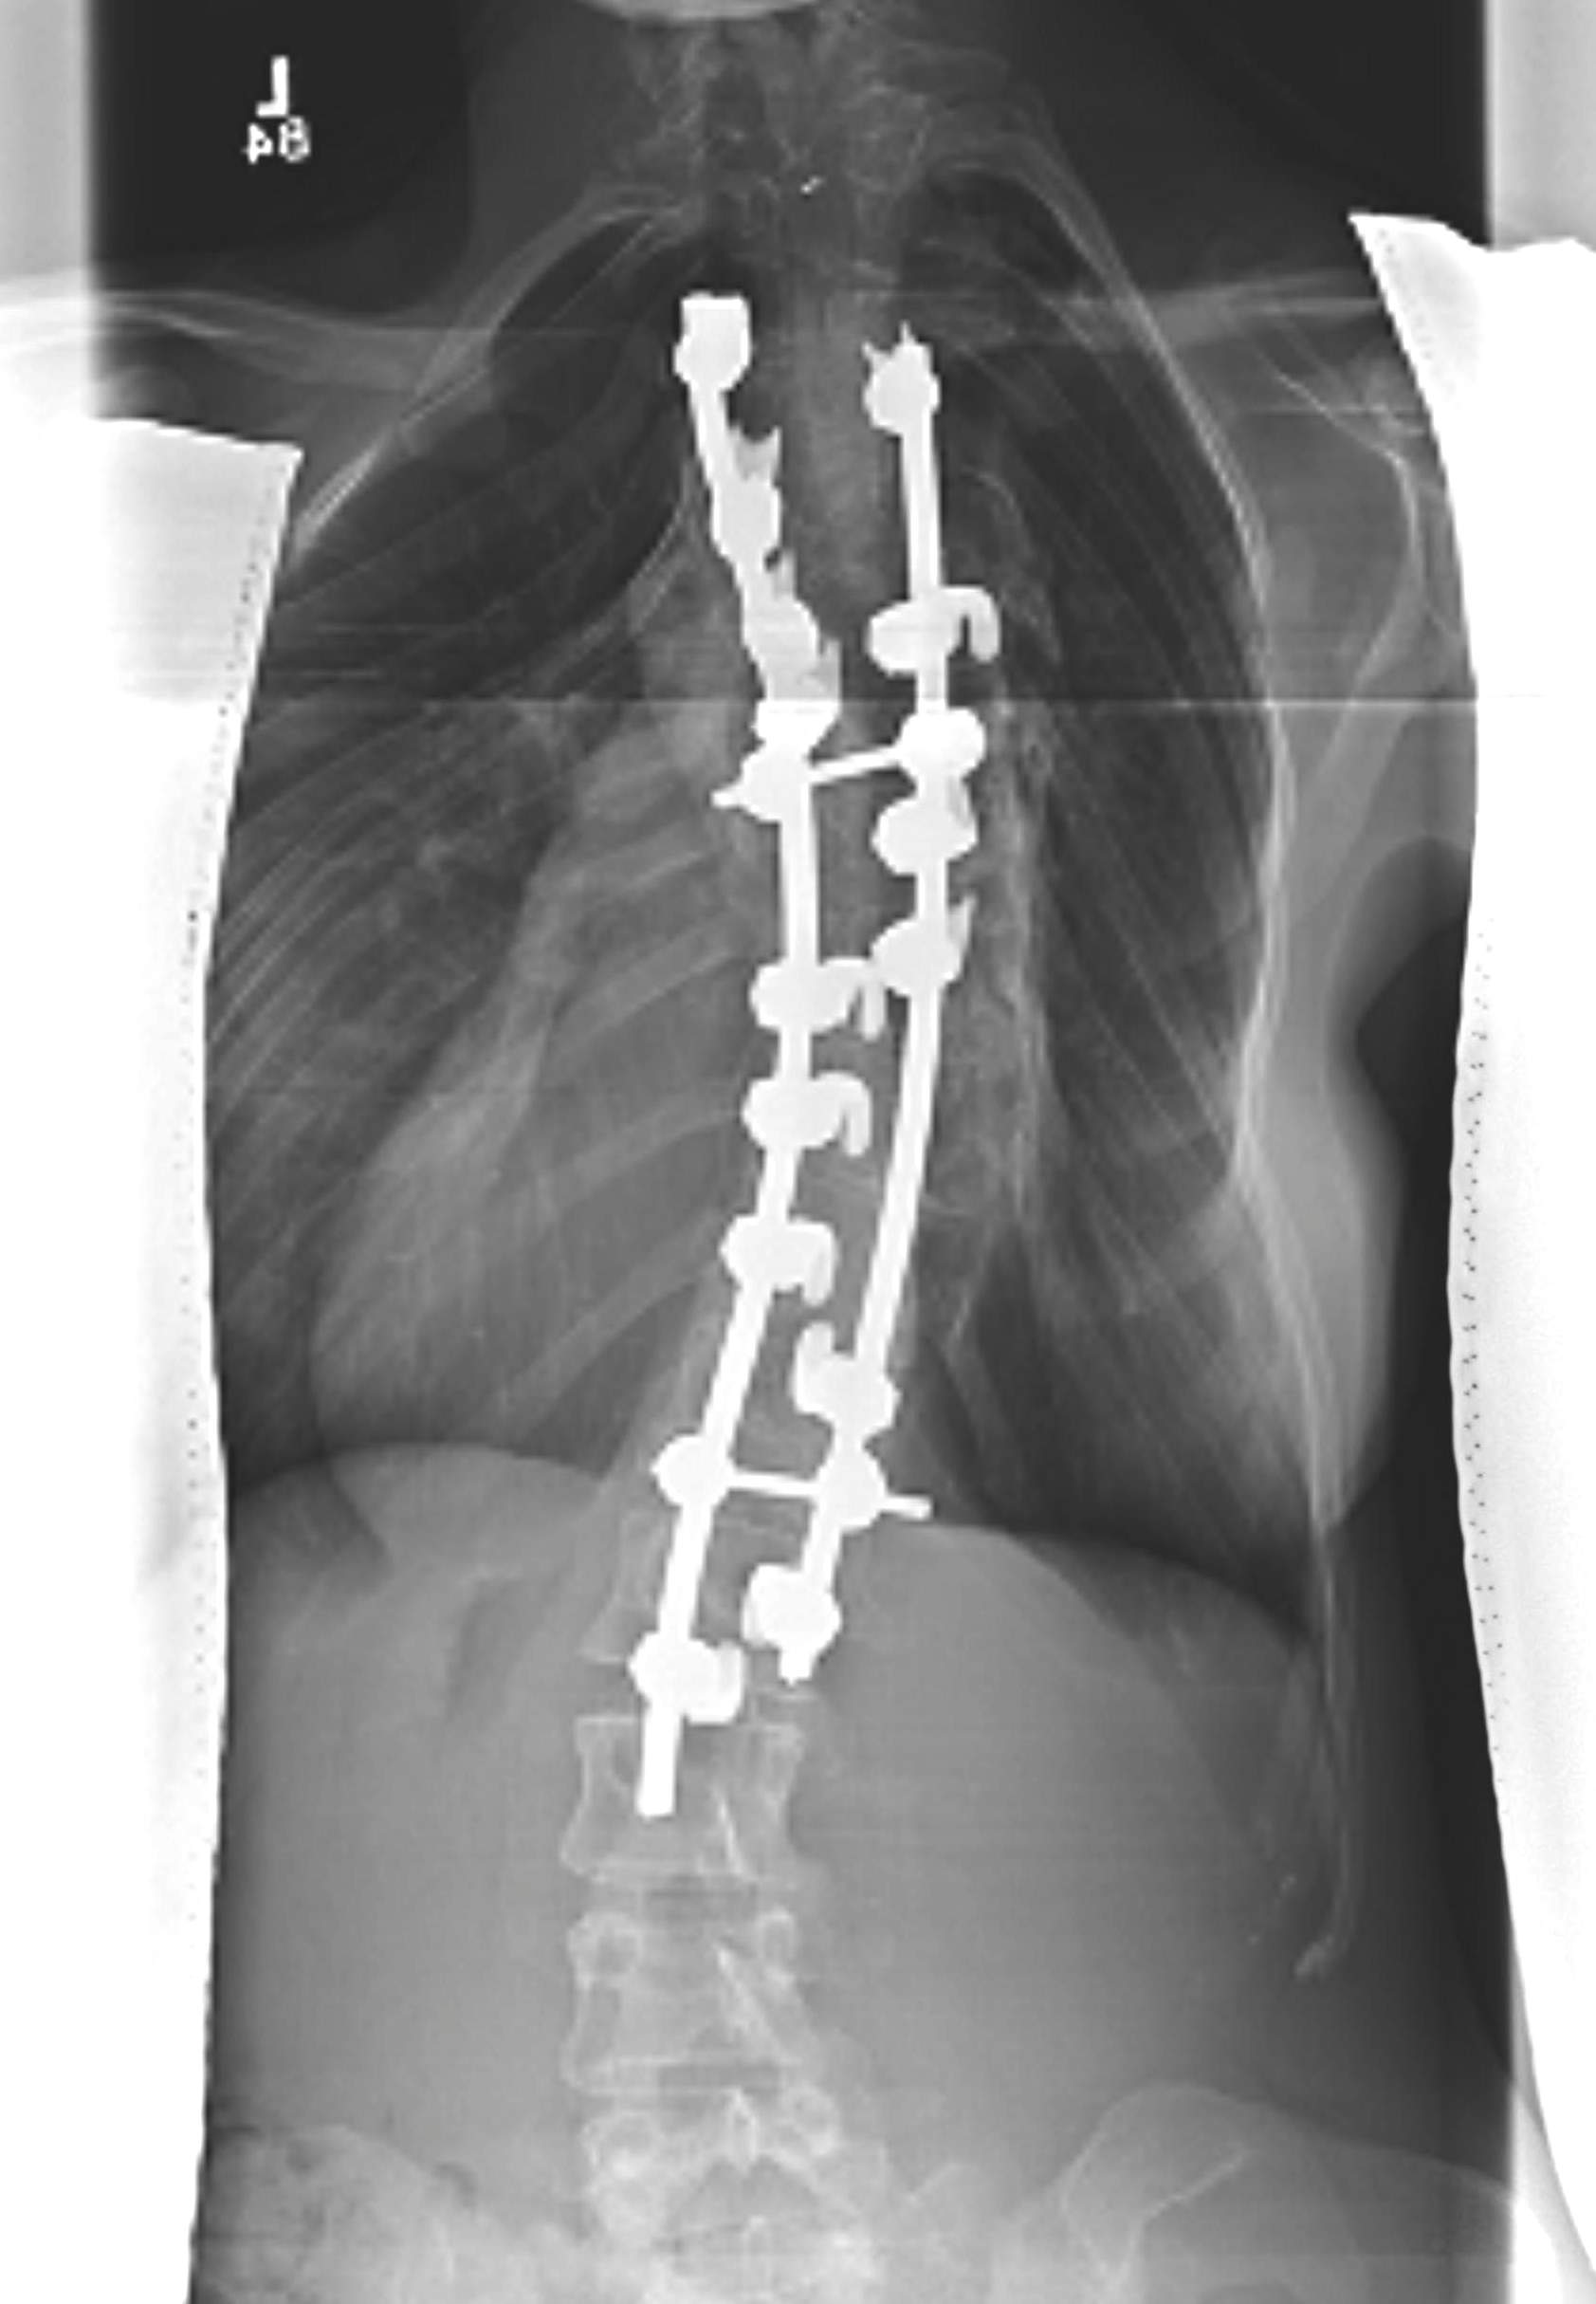

Posterior Instrumented fusion

Multisegmental Hook and Pedicle screw systems

- allows for correction via Compression / Rotation / Distraction

Lenke Type 1

- main thoracic

- posterior stabilisation

- usually limit to T4 as shoulders equal

Lenke Type 2

- double thoracic / MT and PT

- need to instrument to T2

- equalise shoulders